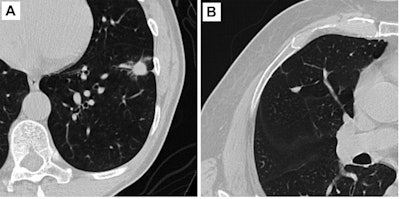

Following up on a successful pilot study, the researchers sought to perform a multicenter clinical validation of the Virtual Nodule Clinic 2.0 software (Optellum). They collected 300 screening and diagnostic chest CT scans -- each containing one 5 mm to 30 mm indeterminate pulmonary nodule -- from two institutions in the U.S. and four in the U.K.

On each of the 300 randomly ordered cases, the readers first estimated malignancy risk of nodules on a 100-point scale and selected a management option. Next, they viewed the AI software's risk malignancy score on a scale of 1 (lowest risk) to 10 (highest risk) and were asked to provide an updated risk estimate and management recommendation.